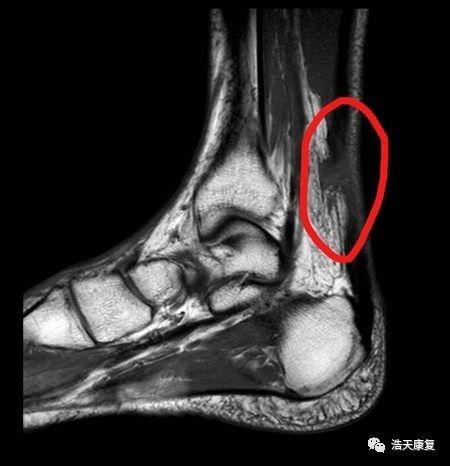

(3)影像学检查:核磁共振成像可发现跟腱断裂,且对于确诊跟腱部分断裂最为有效;超声技术(US)可用来评价两个肌腱断端之间的距离;普通X线平片可用于判断是否伴有跟腱附着部位的急性撕脱骨折。